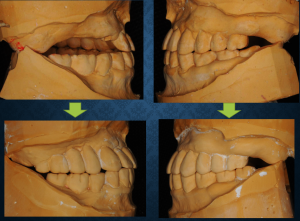

問題は咬合でした。平たく言ってしまうと「ひん曲がっている」状態でした。米国南カリフォルニア大学で補綴を学ばれ仙台で開業されている阿部晴彦先生が開発されたシンラシステムという器具を使って診断したところ、左右で前後的な傾斜が大きく異なっているのが判明しました。残っている歯は、ほとんどが補綴歯(被せものをしている歯)で患者さんもやり替えを希望されました。